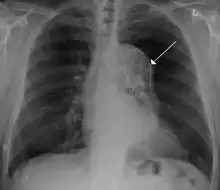

A thoracic aortic stent graft, seen on chest X-ray which was placed during a TEVAR procedure.

Should initial medical management fail or there is the involvement of a major branch of the aorta, vascular surgery may be needed for these type B dissections. Treatment may include thoracic endovascular aortic repair (TEVAR) with or without extra-anatomic bypass such as carotid-carotid bypass, carotid-subclavian bypass, or subclavian-carotid transposition.[14]